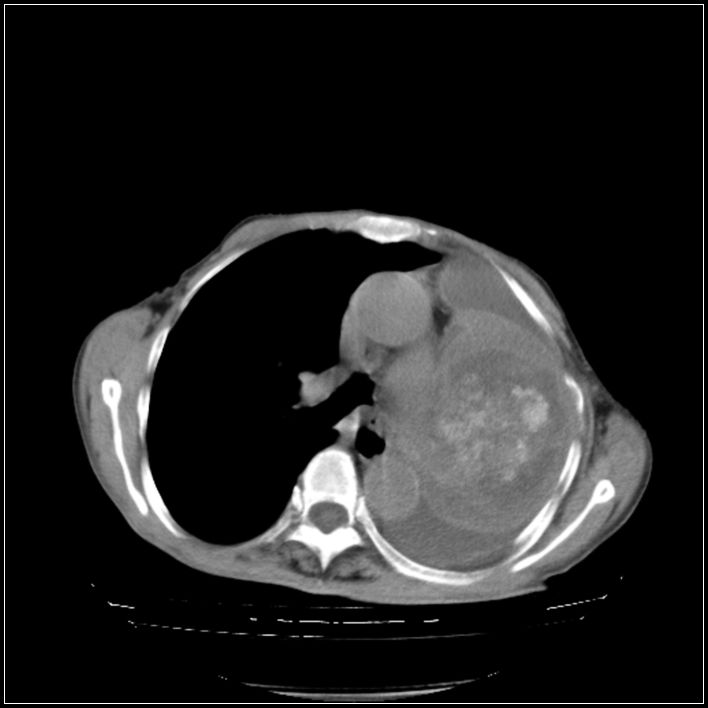

以下是引用影象小辈在2008-5-31 16:25:00的发言:[br]左侧胸腔团状不规则致密影,界欠规整,密度不均匀,其内可见更低密度影及高密度影,并可见包裹性胸腔积液 考虑为1.畸胎瘤 2.肺癌